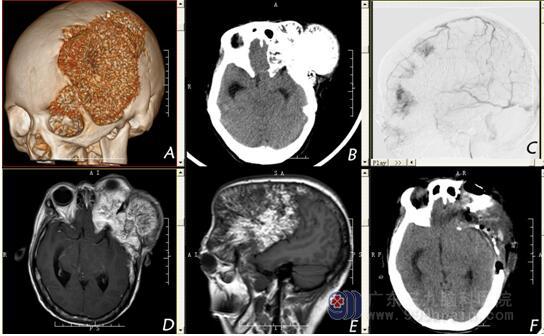

图1 :颅骨海绵状血管瘤的影像学

A:颅骨CT三维重建提示左额颞部巨大占位病变并侵犯左侧眼眶;B: 头颅CT提示额颞部占位呈内低外高混杂密度影,额颞部呈轻度“日光放射” 样改变;C:栓塞术中影像;D、E:头颅MR增强提示左额颞部不均匀强化,可见条形无强化区。F:术后头颅CT提示肿瘤已切除。